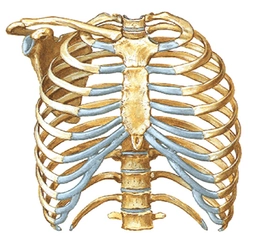

Yanma Hissi ve Nefes Darlığı: Göğsünüzdeki yanma hissi ve nefes alıp vermekteki zorluk, kalp rahatsızlıklarının belirtileri arasında yer alabilir. Bu tür semptomlar, özellikle şiddetli ve ani bir şekilde ortaya çıkıyorsa, dikkate alınması gereken önemli işaretlerdir.

Sol Kol Ağrısı: Sol kolunuzda hissettiğiniz ağrı da kalp rahatsızlıkları ile ilişkilendirilebilecek bir durumdur. Bu tür belirtiler, kalp krizi gibi acil durumların habercisi olabilir, bu yüzden ciddiye alınmalıdır.

Doktora Ne Zaman Başvurmalısınız?: Eğer bu semptomlarınız şiddetli ise, ani bir şekilde başladıysa veya başka belirtilerle (terleme, mide bulantısı, baş dönmesi gibi) birlikteyse, derhal bir sağlık kuruluşuna başvurmalısınız. Ayrıca, bu belirtiler gün içinde devam ediyorsa veya artıyorsa, en kısa zamanda bir doktora görünmelisiniz.